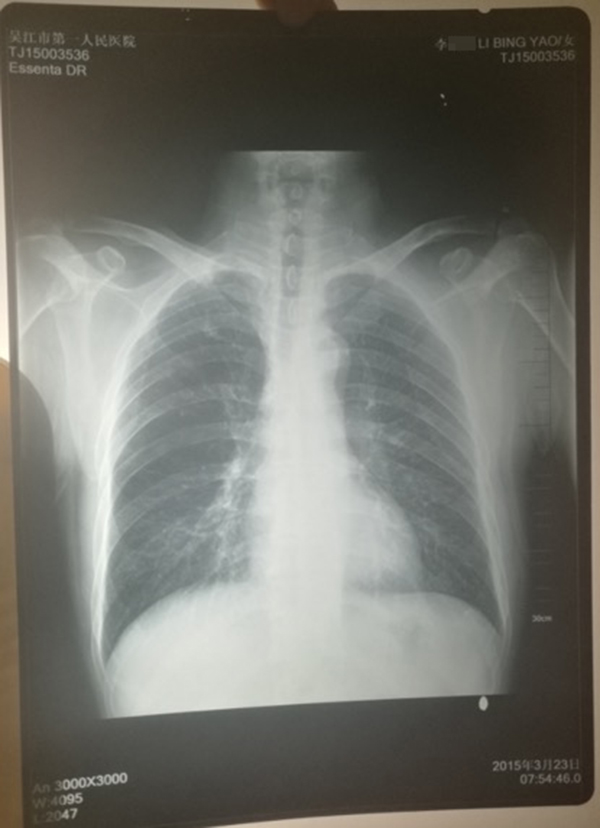

醫院提供的計建宏的“真實胸片”,寫有姓名“李某某”。 受訪人供圖

計云強稱,吳江區第一人民醫院曾提供一份印有“李某某”姓名的胸片,并稱該胸片才是計建宏的“真實影像結果”。

對于“李某某”姓名的胸片,上述吳姓主任稱,經過醫院核查,兩份胸片的結果都是“正常”的,“如果結果是不一樣的話,那么問題就大了,但是因為是一樣的結果,所以不能認為是‘漏診’或‘誤診’。”